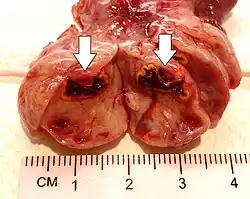

Corpus luteum cyst

A corpus luteum cyst or luteal cyst is a type of ovarian cyst which may rupture about the time of menstruation, and take up to three months to disappear entirely. A corpus luteum cyst does not often occur in women over the age of 50, because eggs are no longer being released after menopause. Corpus luteum cysts may contain blood and other fluids. The physical shape of a corpus luteum cyst may appear as an enlargement of the ovary itself, rather than a distinct mass-like growth on the surface of the ovary.

This type of functional cyst occurs after an egg has been released from a follicle. The follicle then becomes a secretory gland that is known as the corpus luteum. The ruptured follicle begins producing large quantities of estrogen and progesterone in preparation for conception. If a pregnancy doesn't occur, the corpus luteum usually breaks down and disappears. It may, however, fill with fluid or blood, causing the corpus luteum to expand into a cyst, and stay in the ovary. Usually, this cyst is on only one side, and does not produce any symptoms.[1][2]

A ruptured corpus luteum can cause hemoperitoneum with abdominal pain, and is a common condition in women of reproductive age. It may be confused with ectopic pregnancy.[4]